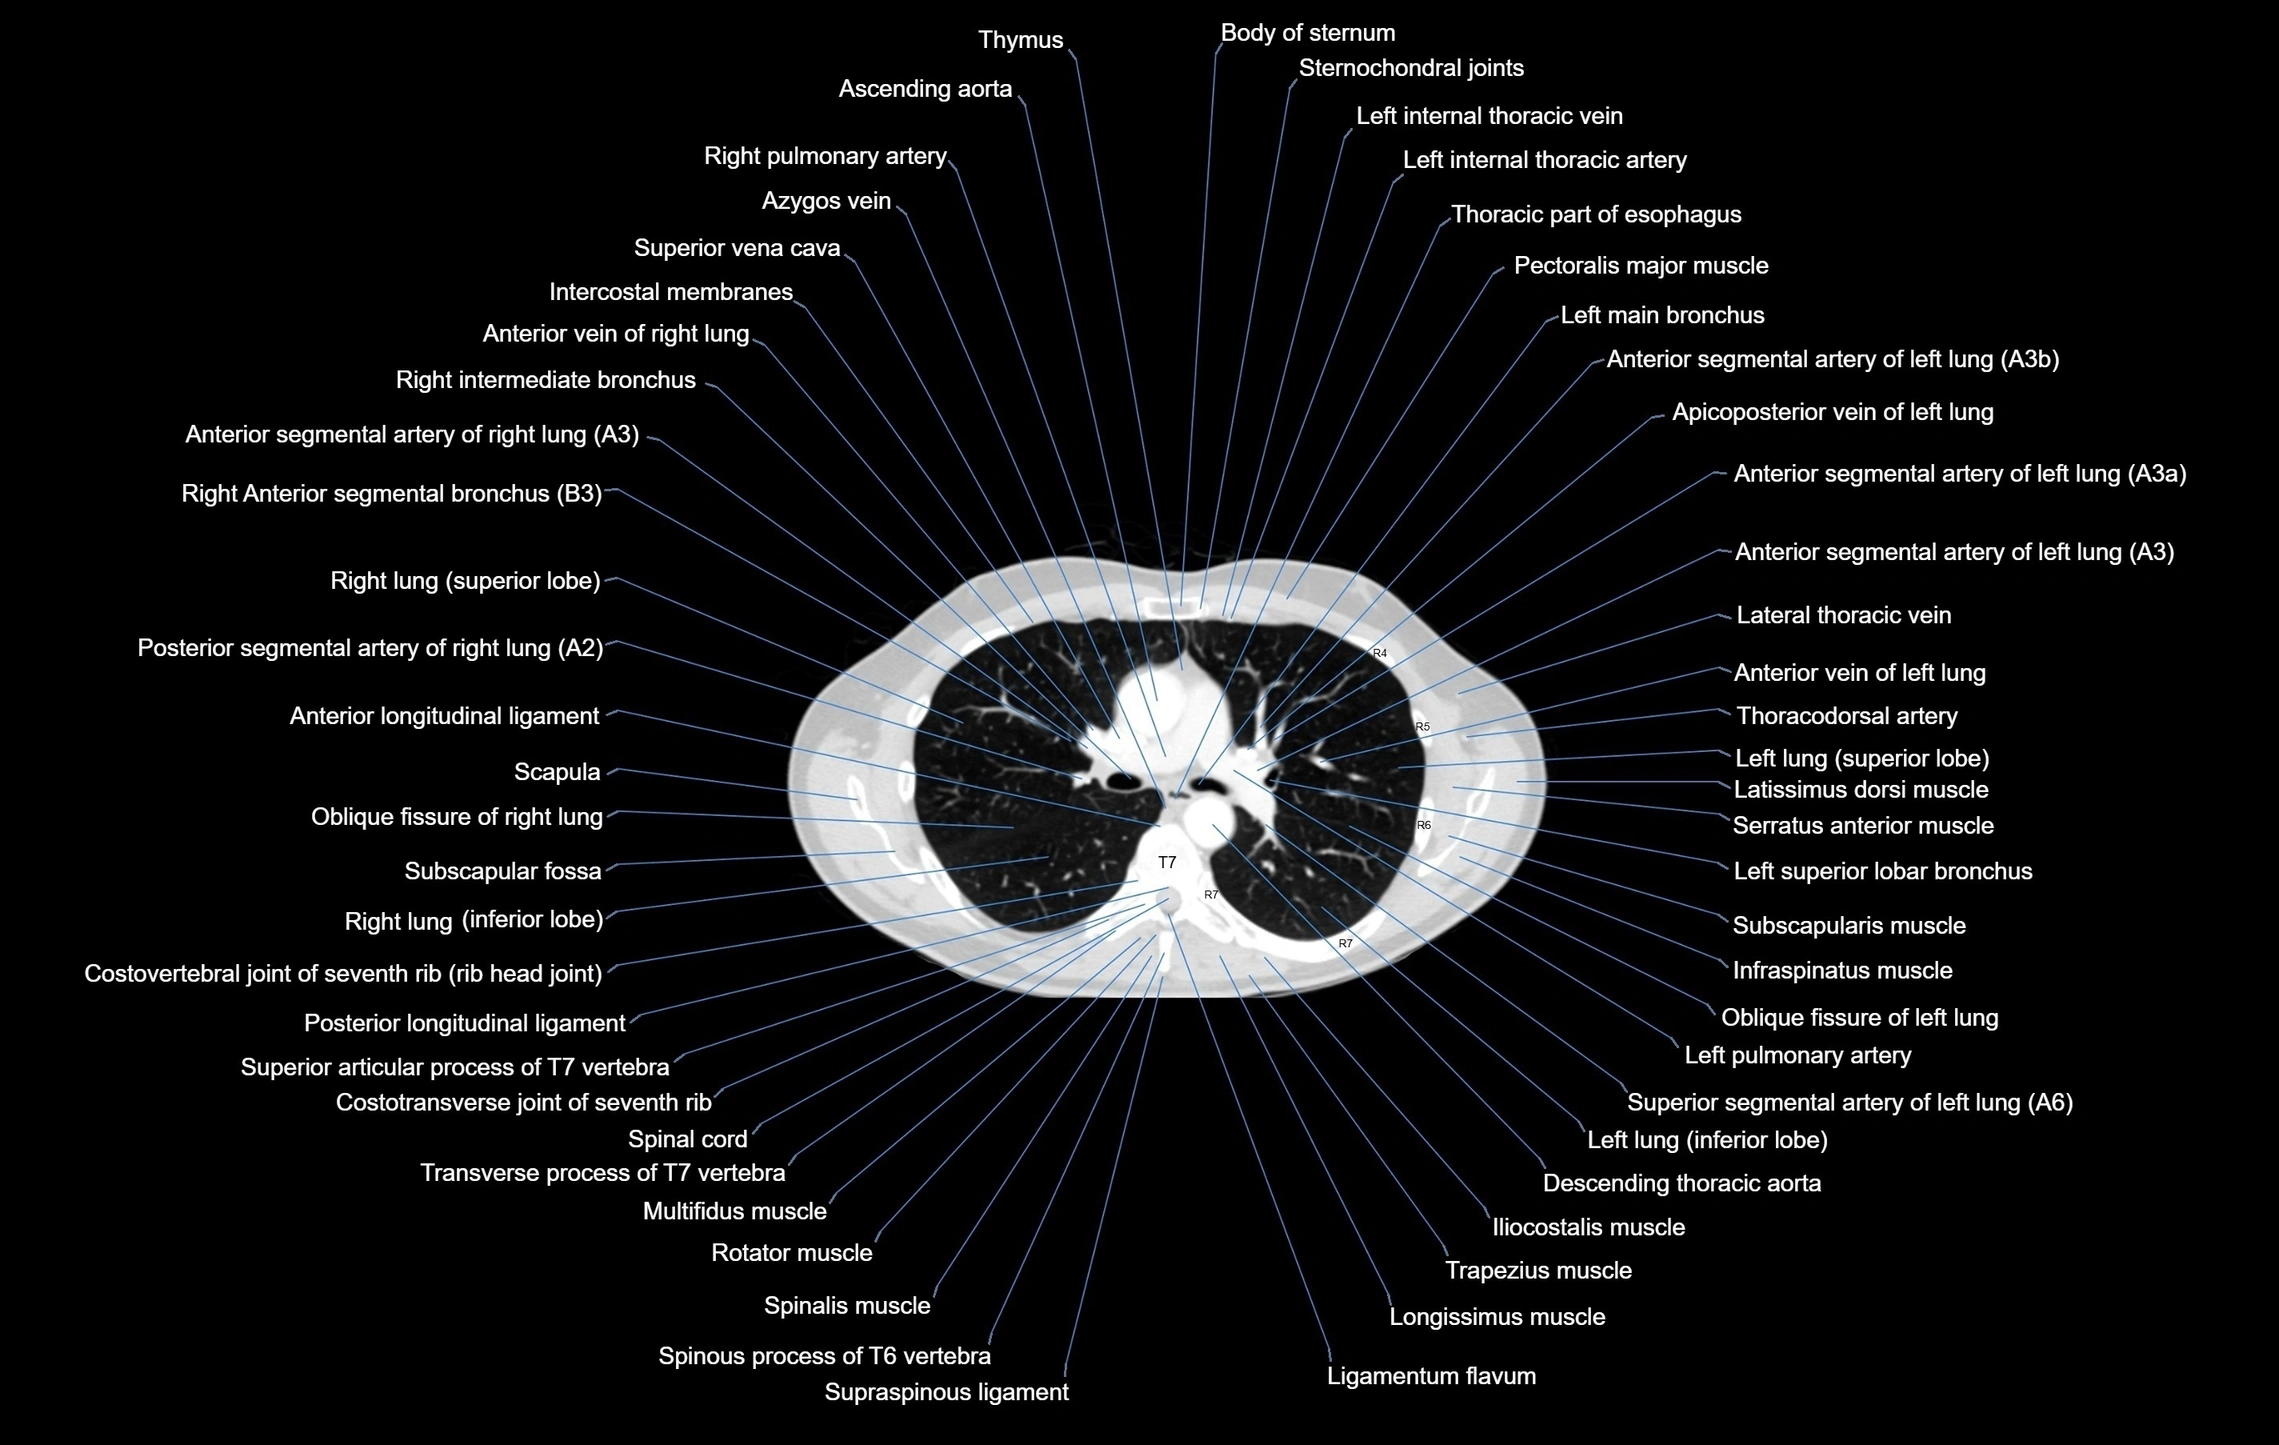

CT images